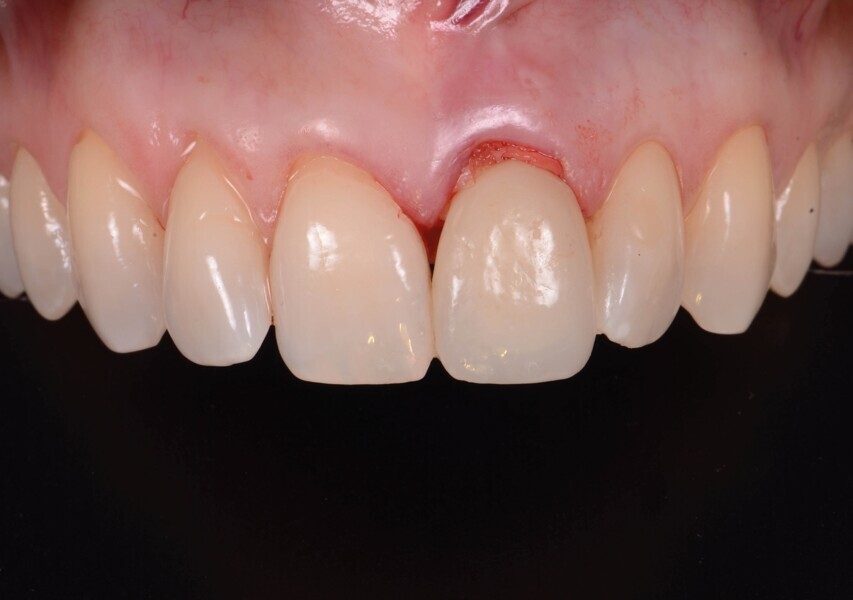

Après un délai de quatre mois postopératoires, la cicatrisation du site est obtenue (Fig. 9) : les tissus mous sont positionnés de manière optimale et les papilles préservées. Le volume osseux est également bien conservé.

Aucune concavité vestibulaire n’est présente et le contour de crête est correct. À ce stade, l’objectif principal est atteint : la cicatrisation post-extractionnelle est atteinte. La priorité passe des lors a la préservation de l’architecture des tissus lors de la phase implantaire. À cet effet, un protocole combinant l’élévation d’un lambeau de petite étendue et une chirurgie guidée avec forage pilote est alors exécuté (Fig . 10).

Un implant (Aadva Regular, GC Tech), avec une connexion conique interne associée au concept du platform switching, est mis en place (Figs. 11–12). La dent provisoire est ensuite collée à nouveau aux dents adjacentes

(Fig. 13a). Au bout de quatre mois, l’ostéointégration de l’implant est obtenue et cette fois encore, les tissus mous sont bien intégrés (Fig. 13b). La phase prothétique peut alors débuter.